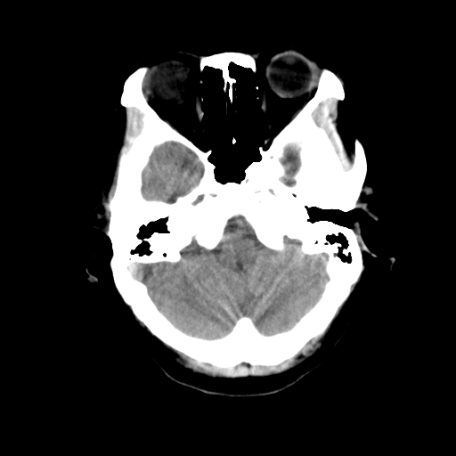

以下是引用深泽交通医院在2009-8-7 12:18:00的发言:[br]有壁结节,考虑囊变型胶质瘤

以下是引用帅河马在2009-8-7 13:50:00的发言:[br][quote]以下是引用深泽交通医院在2009-8-7 12:18:00的发言:[br]有壁结节,考虑囊变型胶质瘤

以下是引用卜一在2009-8-7 15:50:00的发言:[br]囊变性脑膜瘤!支持!

以下是引用随光逐影在2009-8-7 15:58:00的发言:[br]考虑左侧顶叶胶质瘤,不排除左侧镰旁脑膜瘤;建议行进一步检查。